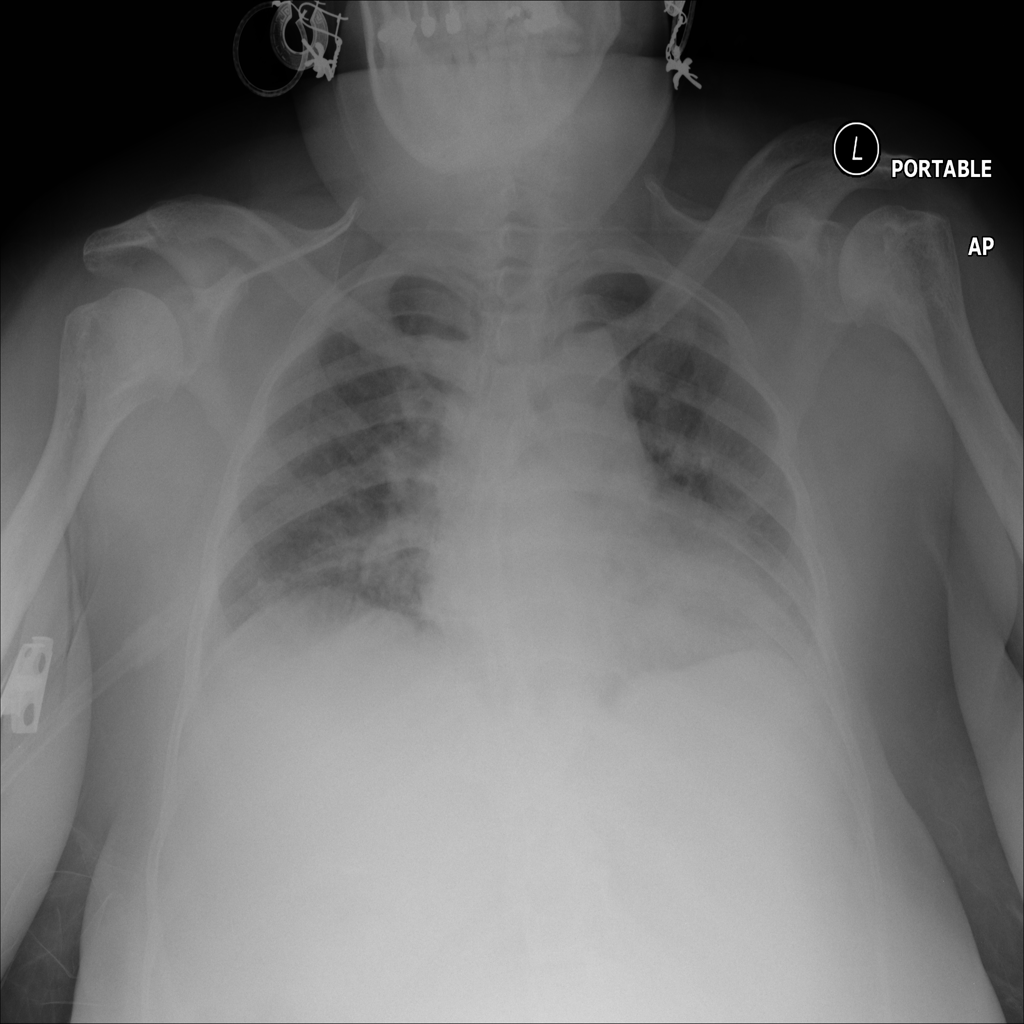

PAT-3384 · IMG-054Atelectasis

PAT-3384 · IMG-054

AP